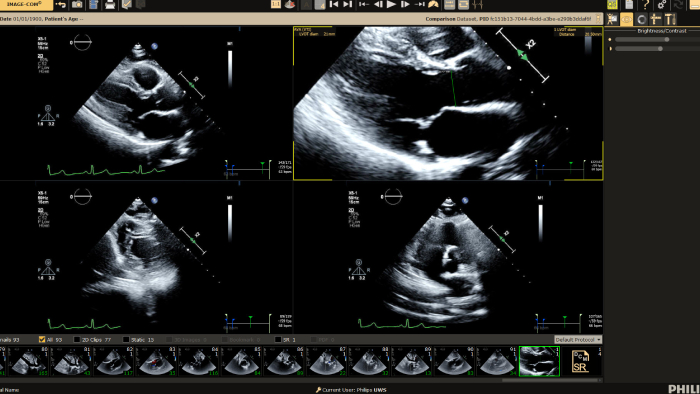

You can still access recordings of 4 full days of hands-on workshops about best practices in multimodality cardiac imaging with expert teams. See first-time-right imaging for cardiac care, including valvular and related diseases, cardiomyopathies, and intracardiac masses and cardiac tumors. Sign up to receive access to these on demand sessions and other news about Philips and cardiac care.

Increase diagnosis confidence and clinical efficiency through superior image quality, advanced quantification tool and automation technology.